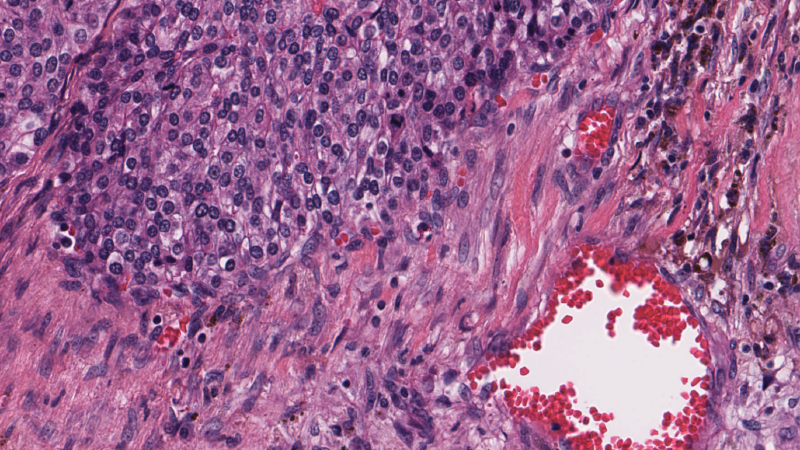

Brain tumors are among the most aggressive and lethal forms of cancer, and early detection is crucial for improving patient outcomes. However, analyzing medical images to diagnose and classify brain tumors presents several challenges due to the sheer size and complexity of whole-slide images (WSIs). In this article, I will share insights from my project, Converting Large Medical Images to Embeddings for Training Classifier Models, where I leveraged deep learning techniques to process high-resolution medical images efficiently. This is not just a technical breakdown but a real-world experience of tackling the problem, highlighting key lessons and takeaways.

Medical images, particularly WSIs, are massive, often exceeding 100,000 pixels in resolution. Traditional image classification methods struggle to process such data due to memory constraints and computational complexity. My goal was to convert these high-dimensional images into meaningful embeddings that could be used for training classifier models to predict immune invasion stages in glioblastoma—a highly aggressive brain tumor.